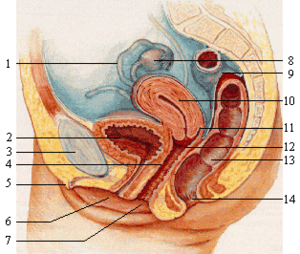

尿道海绵体: 这部分真的是女性的圣蒂了,它就是俗称的 G点

这个由 30几个以上海绵体所组成的部位

又被称为女性摄护腺、尿道旁腺、尿道周腺

这些腺体会分泌一种类似男性摄护腺液的液体

当女性兴奋时,尿道海绵体会膨胀、勃起,推挤阴道壁

有许多女性在此时这个地方会非常敏感

如这时透过阴道向尿道方向仔细摸索

可以感觉到一部分勃起组织这就是所谓的 G点

图中标示为 4 的地方 一直到阴道口附近靠近尿道这边 都可能是 G点所在的位置

(所以不是一个点欧 ,同样的男性们如果要实地探索务必要温柔一点) 抚摸 G点会造成女性射精(潮吹) 不过不是每个女性都是如此,有的女性是经过其它部位的刺激才会射出